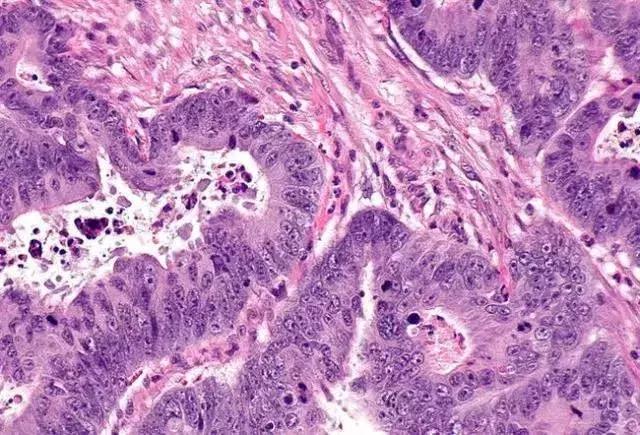

7. 鉴别金标准。病理活检,是鉴别痔疮和直肠癌的金标准。

2. 肠镜。通过肠镜能直视结直肠内部,观察肿块的形态,上下缘及距肛门缘的距离,同时可取病理送检,确定肿块性质及分化程度。位于直肠中、上段癌肿,手指无法触到,采用乙状结肠镜检是一种较好的方法。同样建议有家族史或者年龄达到50岁以上的中老年人应该做定期筛查。